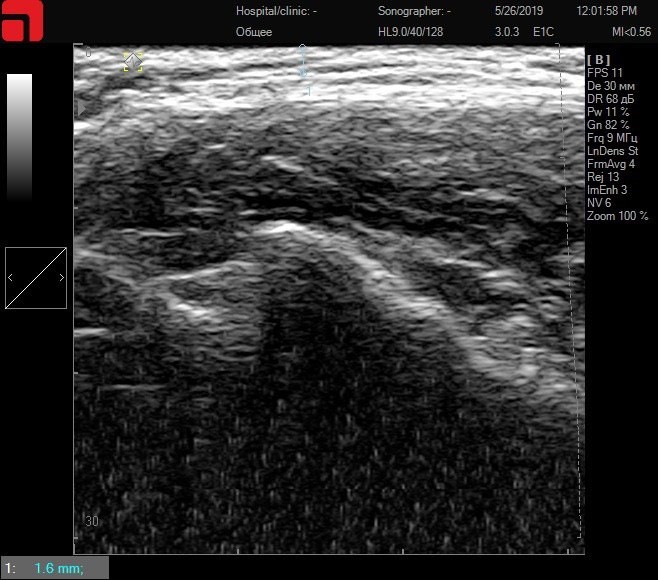

Поверхностное расположение структур SMAS

Тонкая кожа – поверхностное расположение соединительной ткани подкожно-жировой клетчатки и SMAS-слоя

Рис. 1. Тонкая кожа – поверхностное расположение соединительной ткани подкожно-жировой клетчатки и SMAS-слоя.

На данном снимке отмечается, что соединительная ткань, а следовательно, и мишень для процедуры, находятся очень поверхностно в тканях, следовательно, для достижения оптимального результата у данного пациента в лифтинговый протокол будет включаться насадка 1,5 мм (S7), которая обычно направлена на работу с качеством и текстурой кожи.